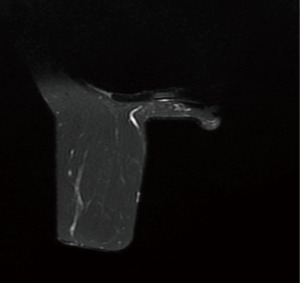

Retrospective review of her imaging revealed the presence of a unilateral RS muscle (Figures 6,7).